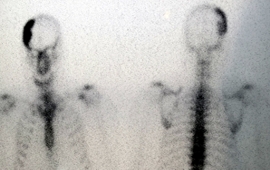

Imagen osteolítica de cráneo vinculada a enfermedad de Paget